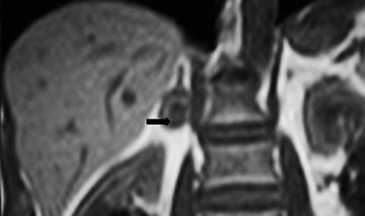

Los sitios más habituales de metástasis son hígado, pulmón, además de la invasión de las estructuras vasculares adyacentes, especialmente de la vena cava inferior, hallazgo que constituye una consideración fundamental al momento de planificar el abordaje quirúrgico (Figura 23 a y b).

Figura 23. Carcinoma suprarrenal derecho. Corte axial de resonancia magnética ponderado en T2 con saturación grasa (a) en que se demuestra una masa suprarrenal derecha con áreas hiperintensas en su espesor probablemente determinadas por necrosis (flecha) y corte coronal en secuencia TRUFISP (b) en que se observa un trombo tumoral que expande el lumen de la vena cava inferior (cabeza de flecha).Puede también presentar invasión directa de otras estructuras vecinas, como riñón, páncreas, bazo y diafragma.